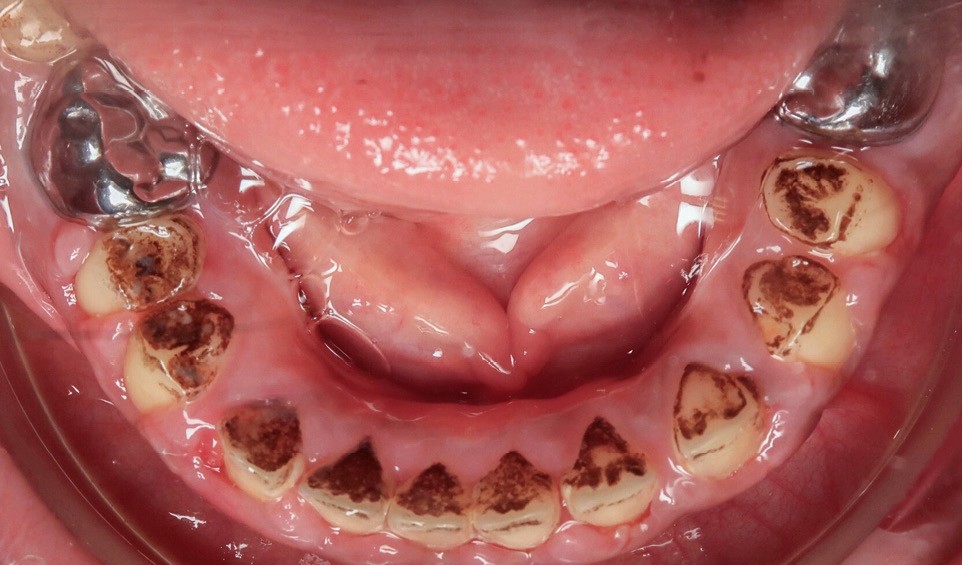

L’examen exobuccal met en évidence un profil dolichofacial et des anomalies majeures de structure dentaire (fig. 1). L’examen intrabuccal (fig. 2) montre :

- une hypoplasie sévère de l’émail ;

- une hyperplasie gingivale inflammatoire ;

- des hauteurs coronaires très réduites ;

- des couronnes pédodontiques sur les premières molaires permanentes ;

- des caries sur 17 et 27 ;

- des défauts d’éruption des quatre deuxièmes molaires permanentes ;

- de nombreux diastèmes et l’absence des dents de sagesse.